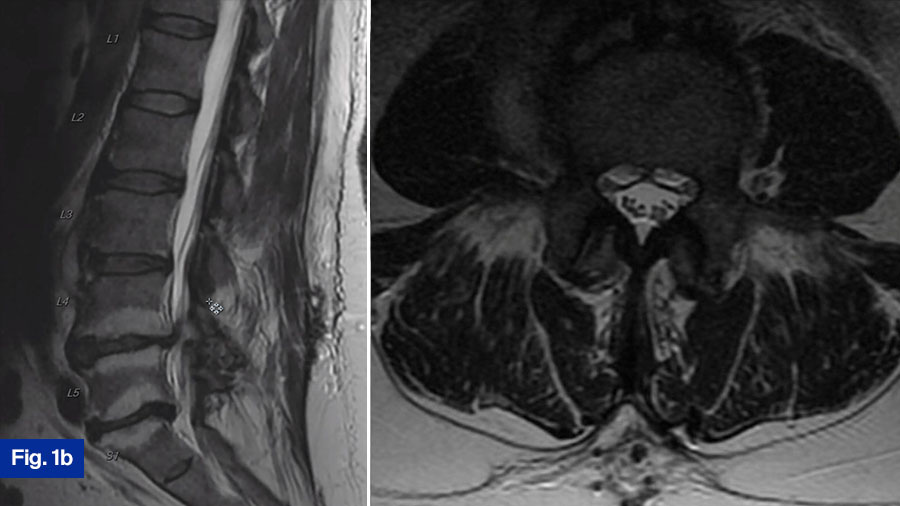

Upon presentation to the ED, he was initially treated with supportive measures/pain control for his back pain. His mention of fevers/chills prompted the ED staff to draw inflammatory labs, which were elevated. Additionally, blood cultures were draw, which eventually grew bacteroides. Due to the elevated blood cultures, and his unrelenting low back pain despite pain control efforts, advanced imaging was obtained. Noncontrasted computed tomography (CT) scan of his spine showed age-appropriate degenerative changes, but was negative for acute findings, and did not show any bony destruction (Figure 1a). A noncontrasted magnetic resonance imaging (MRI) scan of the spine was obtained, which demonstrated a small prevertebral collection without neural compression, and slight end-plate hyperintensity at the L3-L4 level. Additionally, there were L4-L5 and L5-S1 Modic changes (Figure 1b).

In summary, this neurologically intact 56-year-old man presents with a new diagnosis of discitis osteomyelitis based on the CT and MRI findings. I would most often obtain a contrast-enhanced MRI to confirm diagnosis and complete investigations. Typical surgical indications in these cases are 1) neurological deficits, 2) instability, and lastly 3) medical treatment failure. The patient is neurologically intact. The CT scan and MRI show his spine to be stable with preserved alignment and no significant bony destruction. This is a new diagnosis, and full medical management has not been attempted. Furthermore, a bacterial pathogen has been identified allowing for targeted antibiotic therapy. Given the aforementioned factors, I would treat this patient nonoperatively with a full 6 weeks of antibiotics. I would involve the infectious diseases team who would guide targeted antibiotics treatment. Inflammatory markers would then be monitored overtime to determine response to treatment. A growing body of literature suggests that early surgical intervention may lead to improve biological cure rates but given the good clinical status of this patient and the relatively benign appearance of the imaging, I would treat this patient medically.